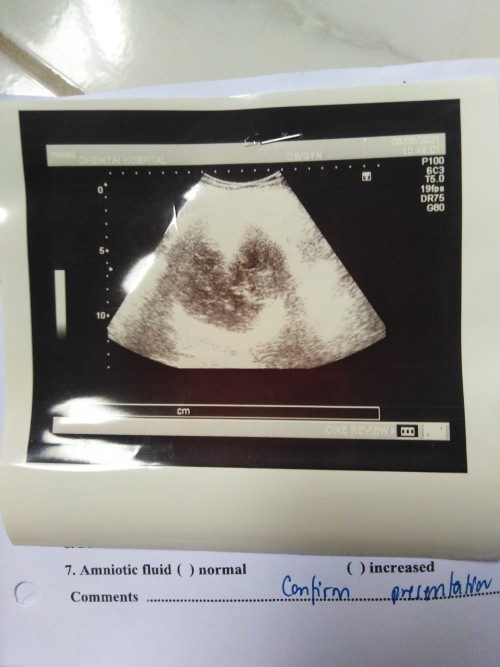

อัลตร้าซาวด์ ที่ รพ.16W3D หมอบอกไม่เจอเพศเด็กยังเล็ก เรยเปลี่ยนมาซาวด์ คลีนิค หมอบอกได้ลูกชาย 😀😀